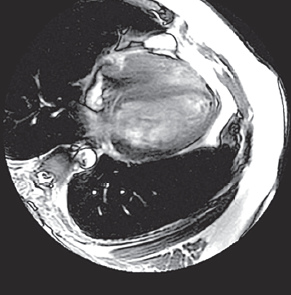

Ahmadreza Karimianpour, DO; Gary P. Miller, MD; Brian W. Zagol, MD

A 73-year-old woman with no known history of coronary artery disease presented to the emergency department with complaints of sudden-onset left-sided substernal chest pain characteristic of myocardial...

11/18/2015